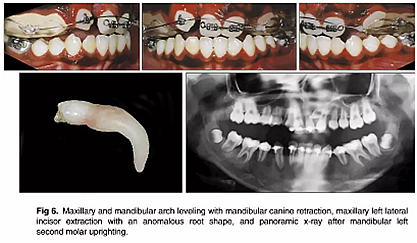

幾個(gè)月后,拔除上頜乳尖牙,應(yīng)用0.018×0.025英寸規(guī)格的亞歷山大固定矯治器; 上頜中切牙的對(duì)齊由0.014英寸的鎳鈦弓絲開始,而上頜左側(cè)尖牙則是腭側(cè)萌出。在下頜弓中,應(yīng)用舌側(cè)弓和第二前磨牙托槽來實(shí)現(xiàn)解除旋轉(zhuǎn)(圖4)。然后,上頜右側(cè)尖牙用0.016英寸的鎳鈦弓絲重新定位,并且使用0.016英寸的不銹鋼片段弓維持中切牙的位置。在下頜弓中,應(yīng)用帶有開放式螺旋彈簧的截面鋼絲直立左側(cè)第二磨牙。它在第一磨牙影響下發(fā)生嚴(yán)重傾斜,受到第三磨牙的壓迫(圖5)。如全景片所示,下頜左側(cè)第二磨牙直立得以實(shí)現(xiàn)(圖6)。1年后,去除上頜擴(kuò)弓器,上下牙弓完全吻合。在上下牙弓中,用0.017×0.025英寸的鎳鈦弓絲進(jìn)行整平。上頜左側(cè)尖牙被移至側(cè)切牙位置; 下頜第一前磨牙被拔除,尖牙開始縮回。

隨后,由口腔頜面外科醫(yī)生(圖6 ; 圖7)拔除左右側(cè)側(cè)切牙,并使用直角弓來旋轉(zhuǎn)上頜磨牙并改善牙弓形態(tài); 在下頜弓中,尖牙的牽引繼續(xù)(圖7)。